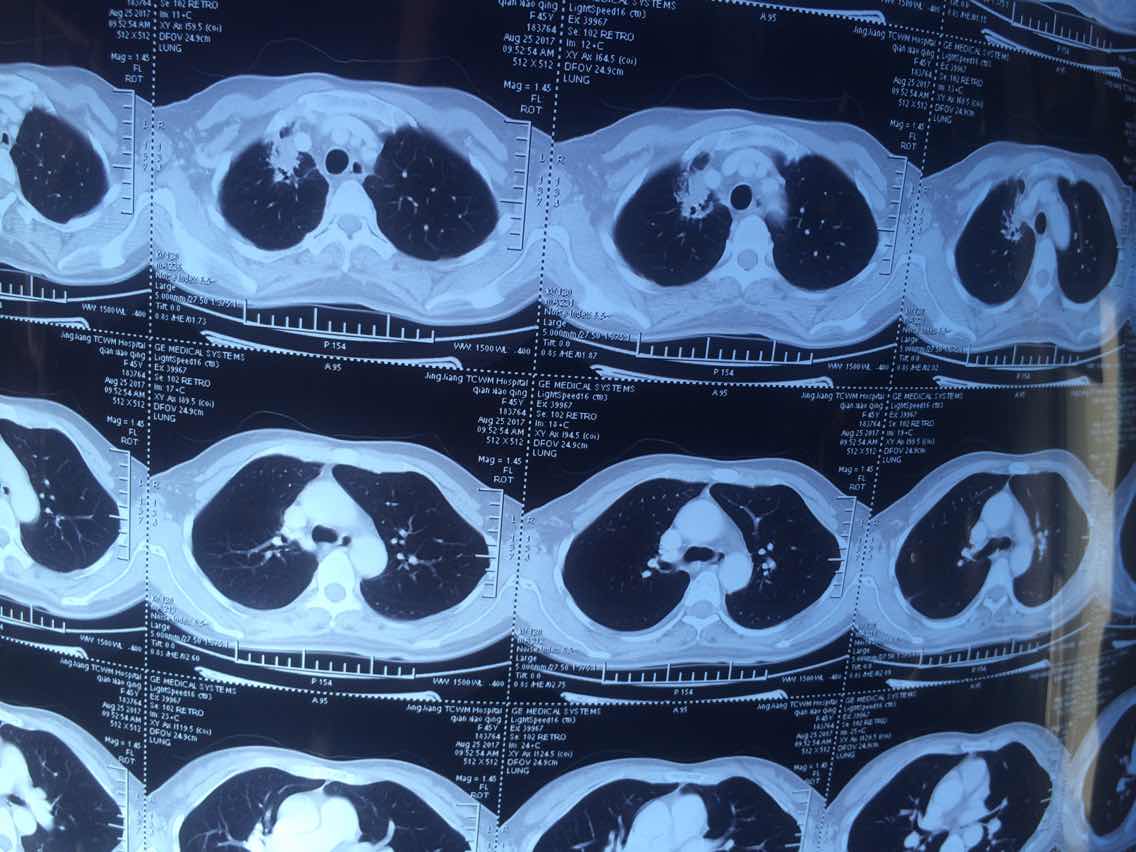

2017.8.25

举报

2017-10-31 10:37:00 有用(0)

回复(0)

2

2017-10-31 10:37:22 有用(0)

3